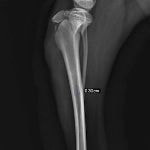

症例3:キルシュナーワイヤーのピンニングによる整復

ペルシャ猫 11ヶ月齢 雄

他院にて左大腿骨遠位の成長板骨折(salter-harrisⅠ型)が認められており、治療相談を目的として来院。当院にて、キルシュナーワイヤーを用いたピンニングにより骨折部位の整復を行いました。術後の経過は良好で、現在も経過観察中です。

術後レントゲン